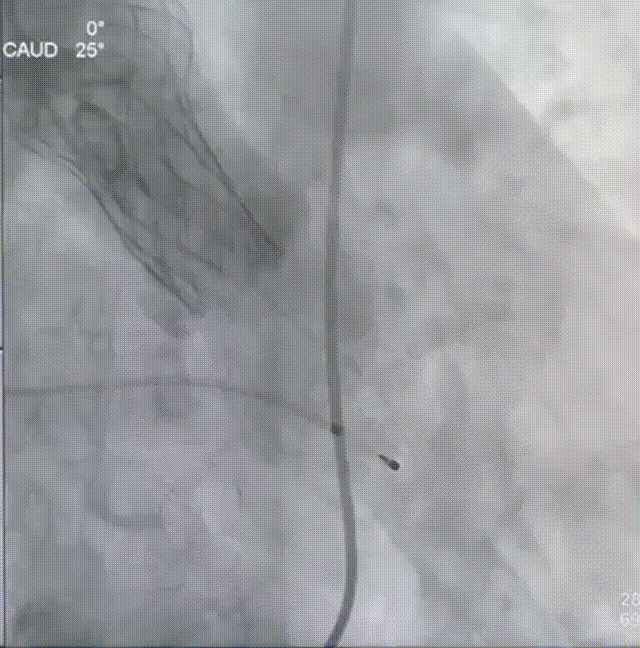

术中操作

主动脉根部造影

22mm球囊预扩

瓣膜定位

瓣膜释放

瓣膜锚定

瓣膜完全释放

24mm球囊后扩

完成植入